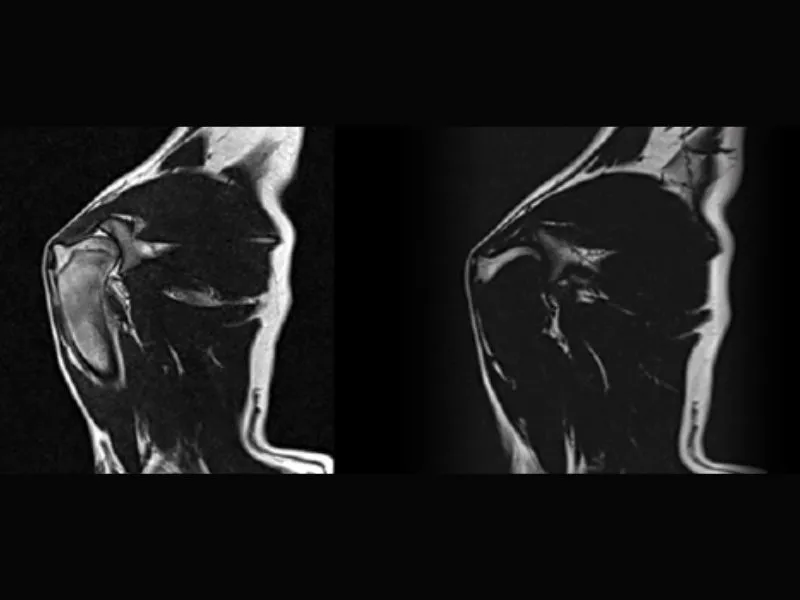

Vet-MR Grande – GE STIR sagittal Dog knee acl fracture